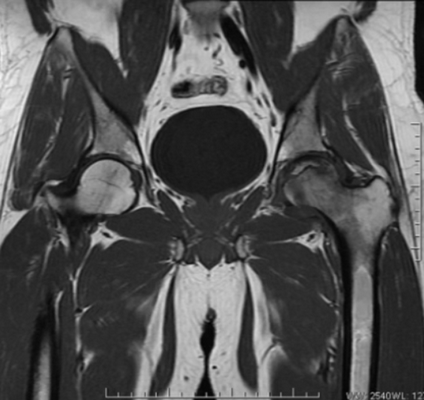

Эпифизеолиз бедер на МРТ

Магнитно-резонансная томография и компьютерное сканирование являются дополняющими способами диагностики, так как часто необходимо оценить и мягкотканные структуры и кости, формирующие сустав. В экстренных ситуациях преимущество у КТ, позволяющей получить результат в течение нескольких минут. Отдаленные последствия травм, опухоли, аваскулярный некроз лучше демонстрирует МРТ. Рентгенографию в современной травматологии используют для поиска грубых повреждений или запущенных процессов, исходящих из костной ткани, при возможности выбора лучше сделать мультиспиральное компьютерное сканирование. Из перечисленных способов визуализации наиболее безопасна МР-томография, так как рентгеновская диагностика подразумевает лучевое воздействие на организм.